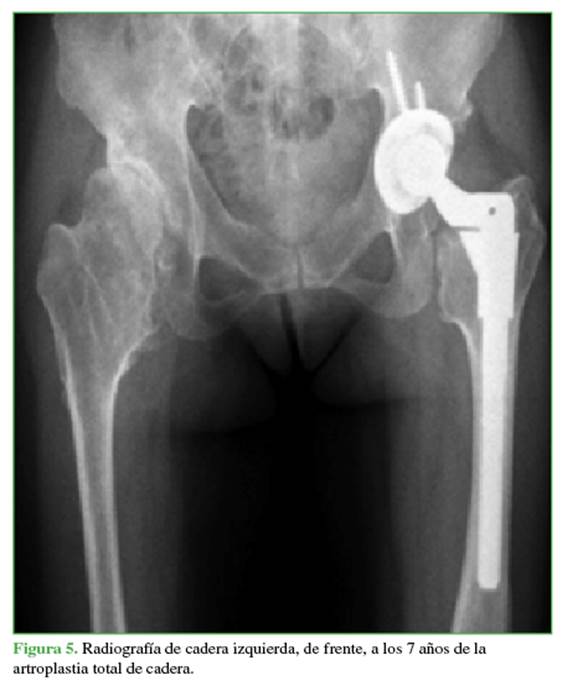

No hubo complicaciones intraoperatorias ni en el posoperatorio inmediato. Siete años después, la paciente continuaba sin síntomas, con una flexión de 120º, una abducción de 40º, una rotación externa de 15º, una rotación interna de 20 º y un puntaje de cadera de Harris de 100. El aspecto radiográfico del implante también era satisfactorio (Figura 5).